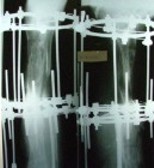

این عمل در مرکز جراحی ولنجک و زیر نظر دکتر حقانی فوق تخصص دست صورت گرفته

تاریخ عمل  پنج شنبه 20 شهریور 1393

شست کوتاه